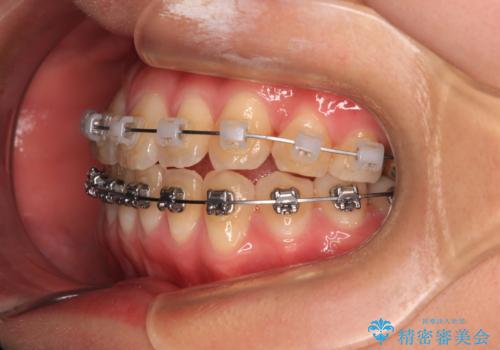

マウスピース矯正が煩わしい ワイヤー装置での非抜歯矯正

上下前歯のデコボコを気にして来院された患者様です。

ワイヤー矯正でもマウスピース矯正でも可能でしたが、短期間で、自身の手を煩わせることなく治療を行いたいとのことで、ワイヤー装置にて矯正治療を行うこととしました。

舌の突出癖により、治療過程でスペースが多くできましたが、舌のトレーニングを頑張っていただき、1年強で終えることができました。